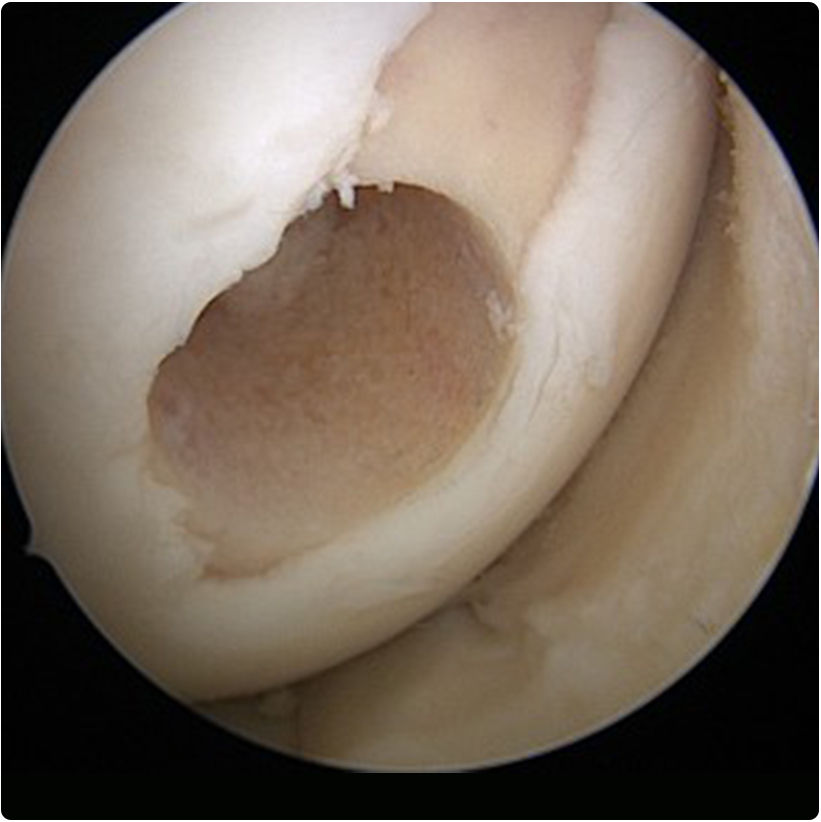

2- Mikrokırık yöntemi: yine artroskopik olarak yapılabilen bu yöntemde kıkırdaktaki hasarlı alanlar temizlenir ve kıkırdağın altındaki kemiğe özel

aletlerle delikler açılır. Böylece kemik iliğinden gelen kan, pıhtı ve birçok hücreye dönüşme yeteneğindeki kök hücreler hasarlı alanı doldurabilir. Bir süre sonra orijinal kıkırdak dokusu kadar güçlü olmasa da ona benzeyen bir dokuyla çukur doldurulmuş olur.  Bu girişim yük taşıyan bir alana uygulandı ise 4-6 hafta kadar yük vermeyi kısıtlayan bir fizyoterapi uygulanır.